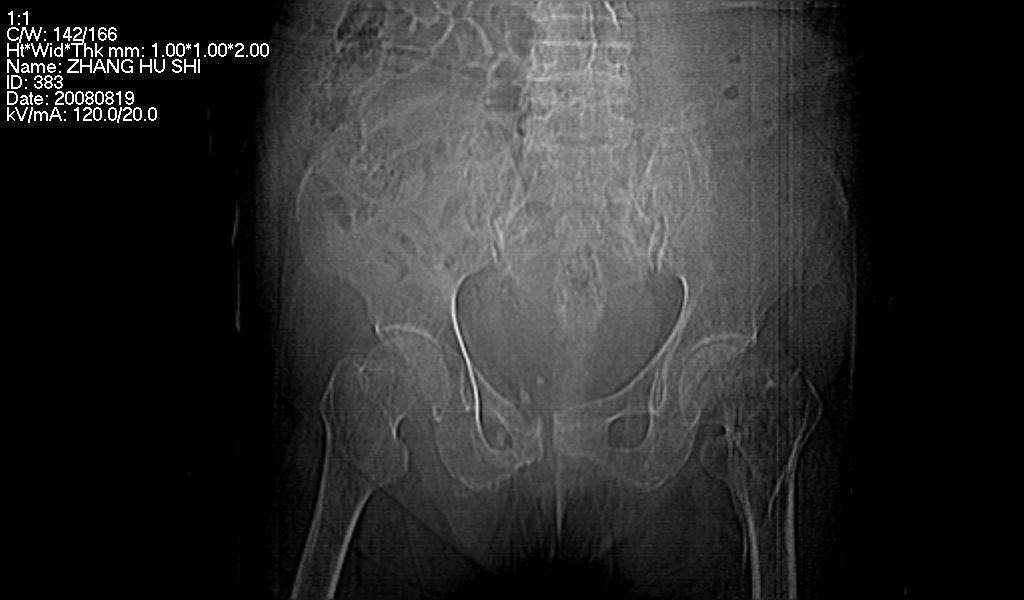

标题: CT15287:女 93岁 右髋关节疼痛 原左侧粗隆间骨折 CT发现右耻 [打印本页]

标题: CT15287:女 93岁 右髋关节疼痛 原左侧粗隆间骨折 CT发现右耻